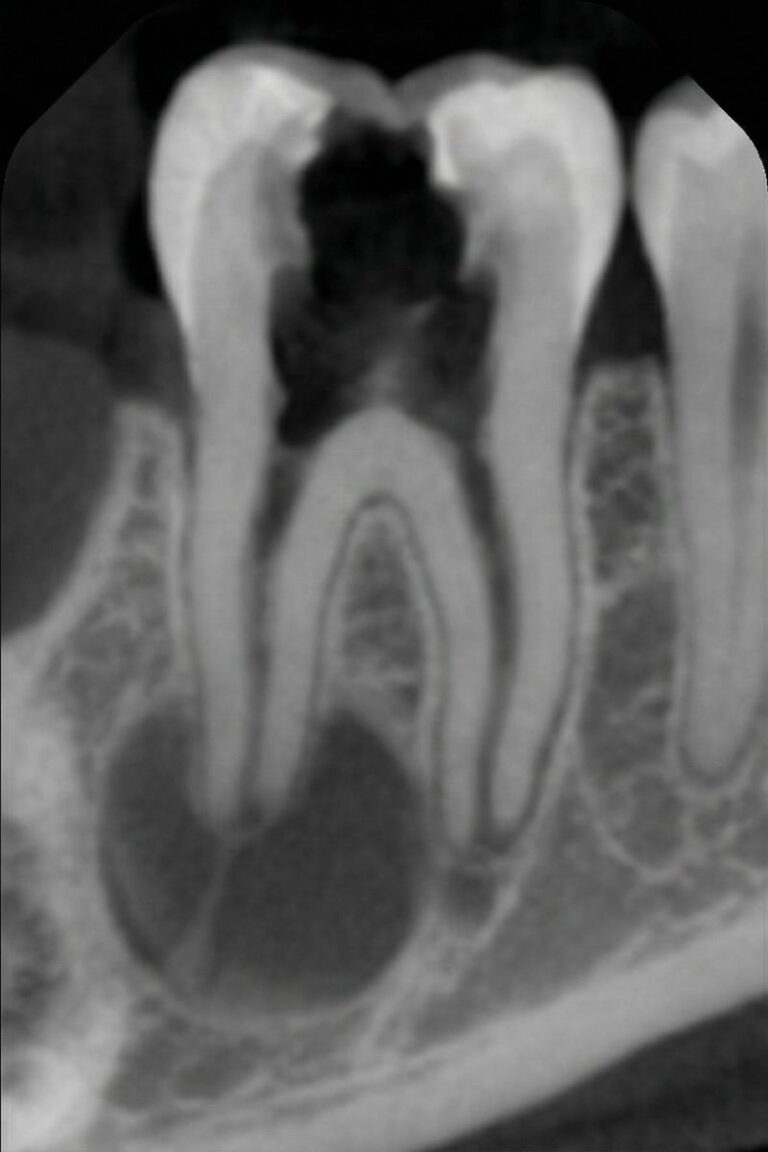

Root canal therapy is an endodontic procedure that removes diseased or inflamed pulp, disinfects the canals and seals them with gutta‑percha. After the canals are cleaned, the tooth is rebuilt with a filling or crown for strength and function. We offer retreatment root canals when previous therapy fails, a pulpotomy to partially remove the nerve in developing teeth and an apicoectomy (endodontic surgery) to remove infection at the root tip.

Digital 3‑D imaging, rotary instruments and ultrasonic irrigation help us clean canals thoroughly and perform efficient single‑visit treatments.